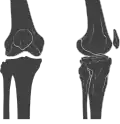

![]() Human knees | |

![]() Right knee (front-right view) | |